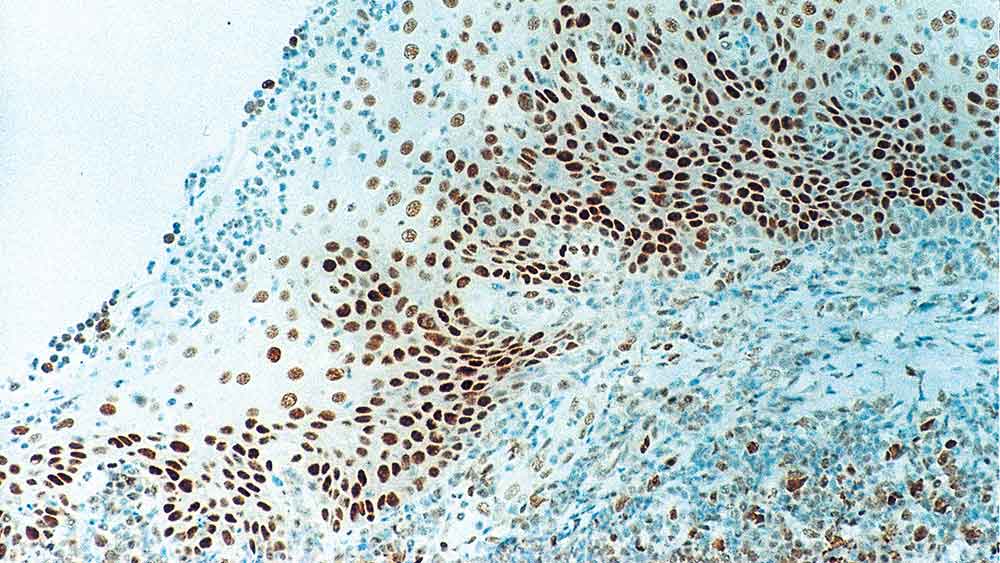

IHC-P analysis of human tonsil tissue using GTX01934 Rb antibody [13A10]. Note intense nuclear staining of epithelial cells.